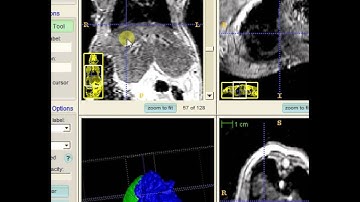

Mouse Organ Segmentation with ITK Snap Part 3